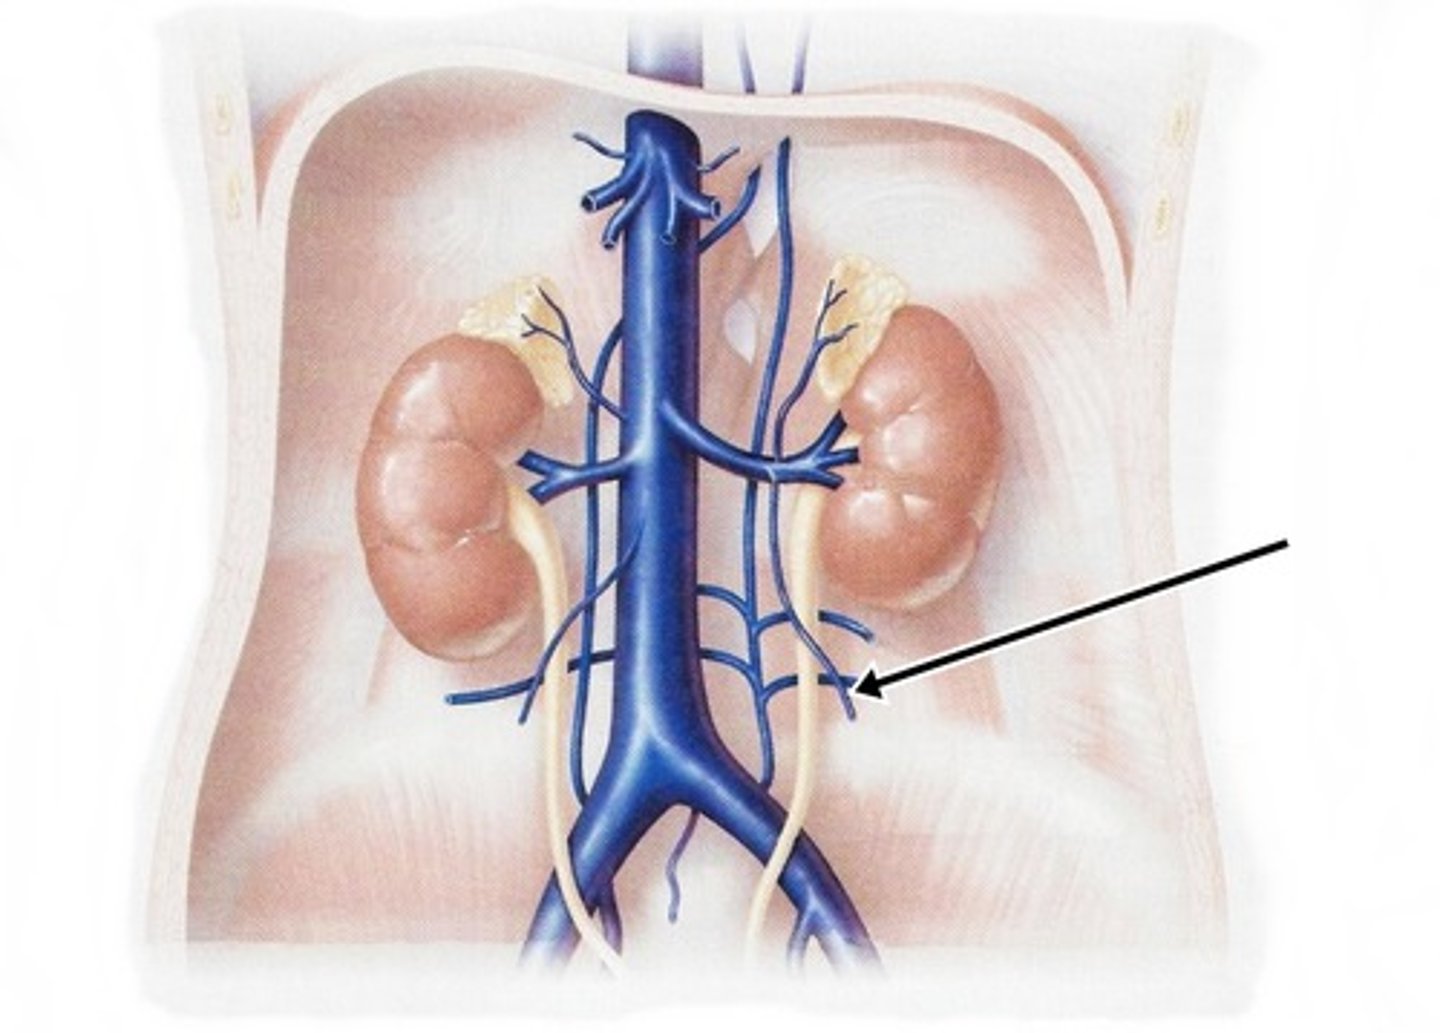

renal veins

left gonadal vein

right gonadal vein